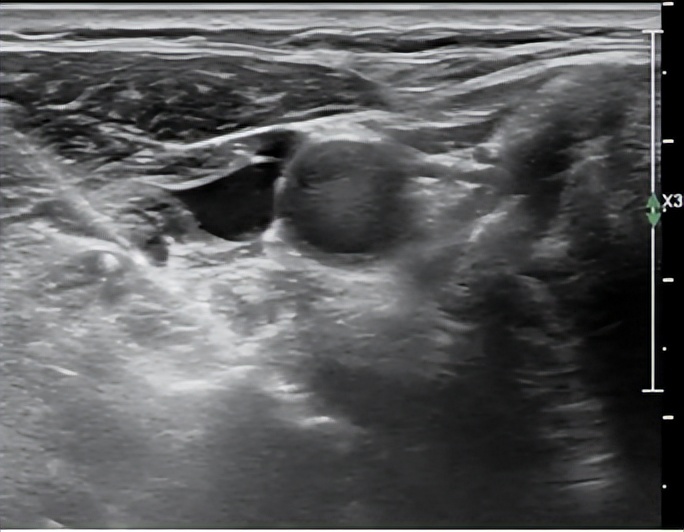

张红主任、孙媛媛医师充分完善术前准备后在CT室姜永宏主任、创伤与老年脊柱科钱立雄副主任医师的协作下,超声引导下避开颈动静脉、神经等重要结构,将穿刺针实时精准穿刺入目标颈椎间盘,CT验证穿刺针针尖位置准确后注药,术中无出血,术后即刻患者头晕、心慌、胸闷等症状明显缓解,责任椎间盘明确,为临床术前精准诊断提供有力依据。

超声医学科(北院区)张红主任行超声引导下颈椎间盘穿刺术